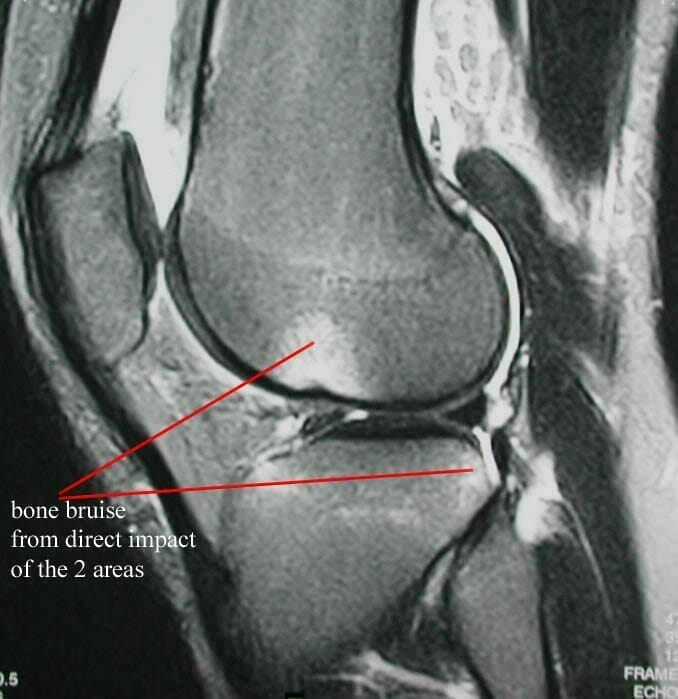

MRI scanning is very good at showing soft tissues, but is poorer at showing bone. It is commonly used to diagnose meniscal injuries, ligament injuries, articular cartilage damage, bone tumours, soft tissue tumours and can also show up other intra-articular abnormalities. MRI scanning is not 100% accurate. It will occasionally miss pathology and it will also occasionally show up abnormalities which are not clinically relevant. For example in the case of meniscal tears, MRI scanning is said to be between 90 and 95% accurate in detecting meniscal tears. Studies have been done which show that an examination by a well-trained and experienced knee surgeon is as accurate as MRI scanning in diagnosis meniscus injuries and tears. Because of the accuracy of MRI scanning, it is commonly used and in my view over used, for people with various complaints of knee pain. Clinically, prior to requesting an MRI scan, the surgeon should have a diagnosis or a list of diagnoses to confirm or refute. In most knee conditions, MRI scanning is not routinely required to make a diagnosis.

An area where MRI scanning is now starting to develop specifically is in the area of imaging of articular cartilage which has great relevance for articular cartilage injury, such as chondral and osteochondral defects, as well as cartilage transplantation procedures. Current MRI scanners do not have the power to provide the resolution that is always needed for good articular cartilage imaging. However, I am fortunate to have the ability to access one of the few 3 Tesla (the higher the Tesla value of an MRI scanner, the more power it is and the greater resolution that can be obtained from it. Most MRI scanners and 1-1.5 Tesla), scanners with which we are currently devising research protocols. We are however, using it in a clinical situation for articular cartilage imaging, where it is proving to be highly valuable.